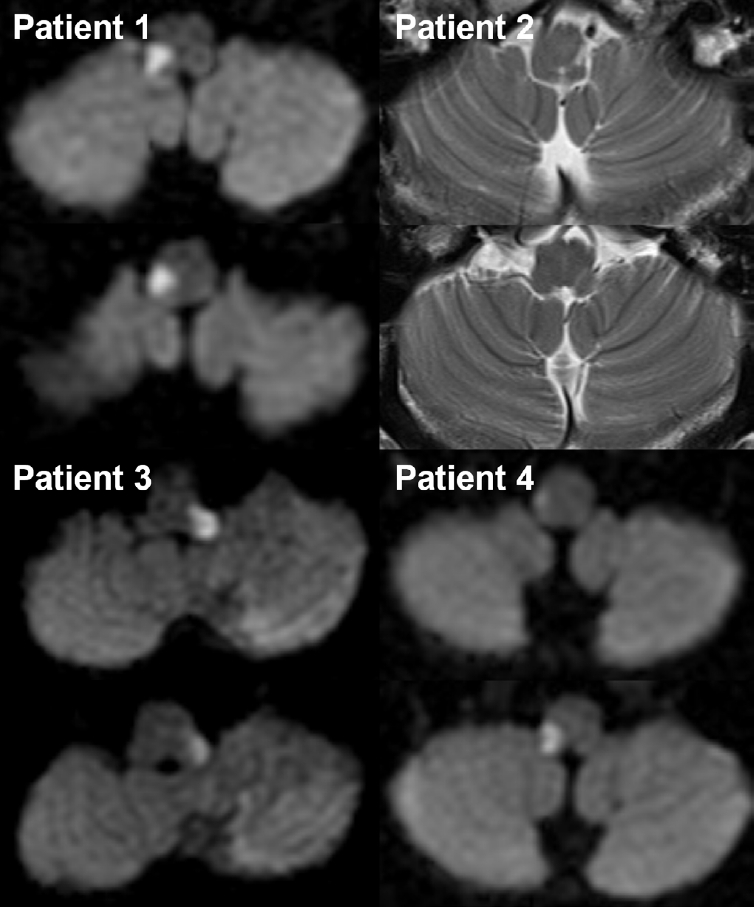

Neuroimaging of the four patients who presented with dorsolateral medullary infarction.

Diffusion-weighted (patients 1, 3, and 4) or T2-weighted (patient 2) brain magnetic resonance imaging shows high signal intensity lesions involving the unilateral dorsolateral medulla. An additional lesion in the ipsilateral cerebellar hemisphere is also observed in patient 3.

Notably, all patients showed at least one focal neurological sign during the acute stroke phase, which preceded the onset of the headache. These included sensory loss on the ipsilateral hemiface (100%), sensory loss on the contralateral hemibody, ipsilateral limb ataxia and/or truncal ataxia, and spontaneous horizontal and torsional nystagmus beating toward the contralesional side. Based on the neuroimaging results of the patients, a clinico-anatomical correlation analysis invariably revealed the involvement of the trigeminal spinal tract and nucleus, as well as the adjacent spinothalamic tract, inferior cerebellar peduncle, and vestibular nucleus.